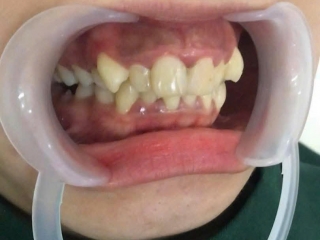

Khám răng sớm cho trẻ – Ngăn ngừa lệch khớp cắn, giúp răng phát triển đều

Không ít bậc phụ huynh nghĩ rằng răng sữa của trẻ rồi cũng sẽ thay, nên thường chưa chú trọng đến việc khám răng định kỳ cho con. Tuy nhiên, sự thật là những vấn đề nhỏ ở giai đoạn răng sữa nếu không được phát hiện và xử lý kịp thời có thể dẫn đến nhiều hậu quả lâu dài: răng mọc lệch, khớp cắn sai, hàm phát triển không cân đối.

Chính vì vậy, các chuyên gia nha khoa luôn khuyến nghị: Khám răng sớm cho trẻ là cách tốt nhất để đảm bảo sự phát triển đều đặn, khỏe mạnh và thẩm mỹ cho hàm răng sau này. Đây không chỉ là chăm sóc răng miệng, mà còn là cách đầu tư cho tương lai và sự tự tin của con.